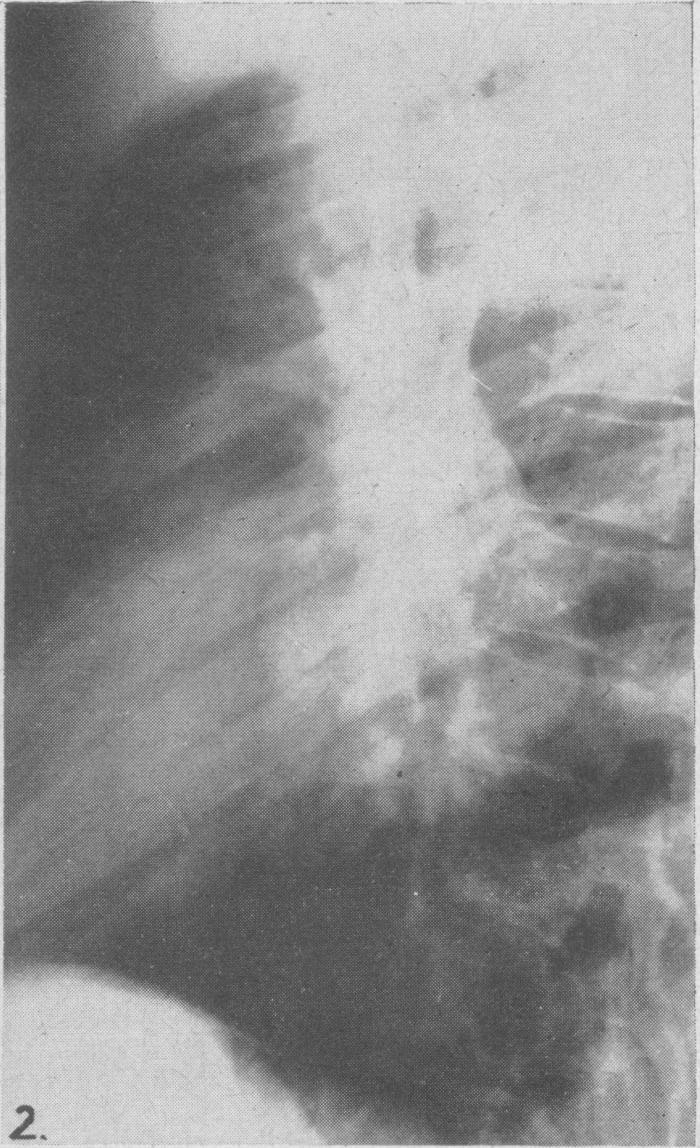

Ciliated columnar epithelial cyst of the mediastinum.

Can Med Assoc J. 1949 Nov;61(5):525-8.